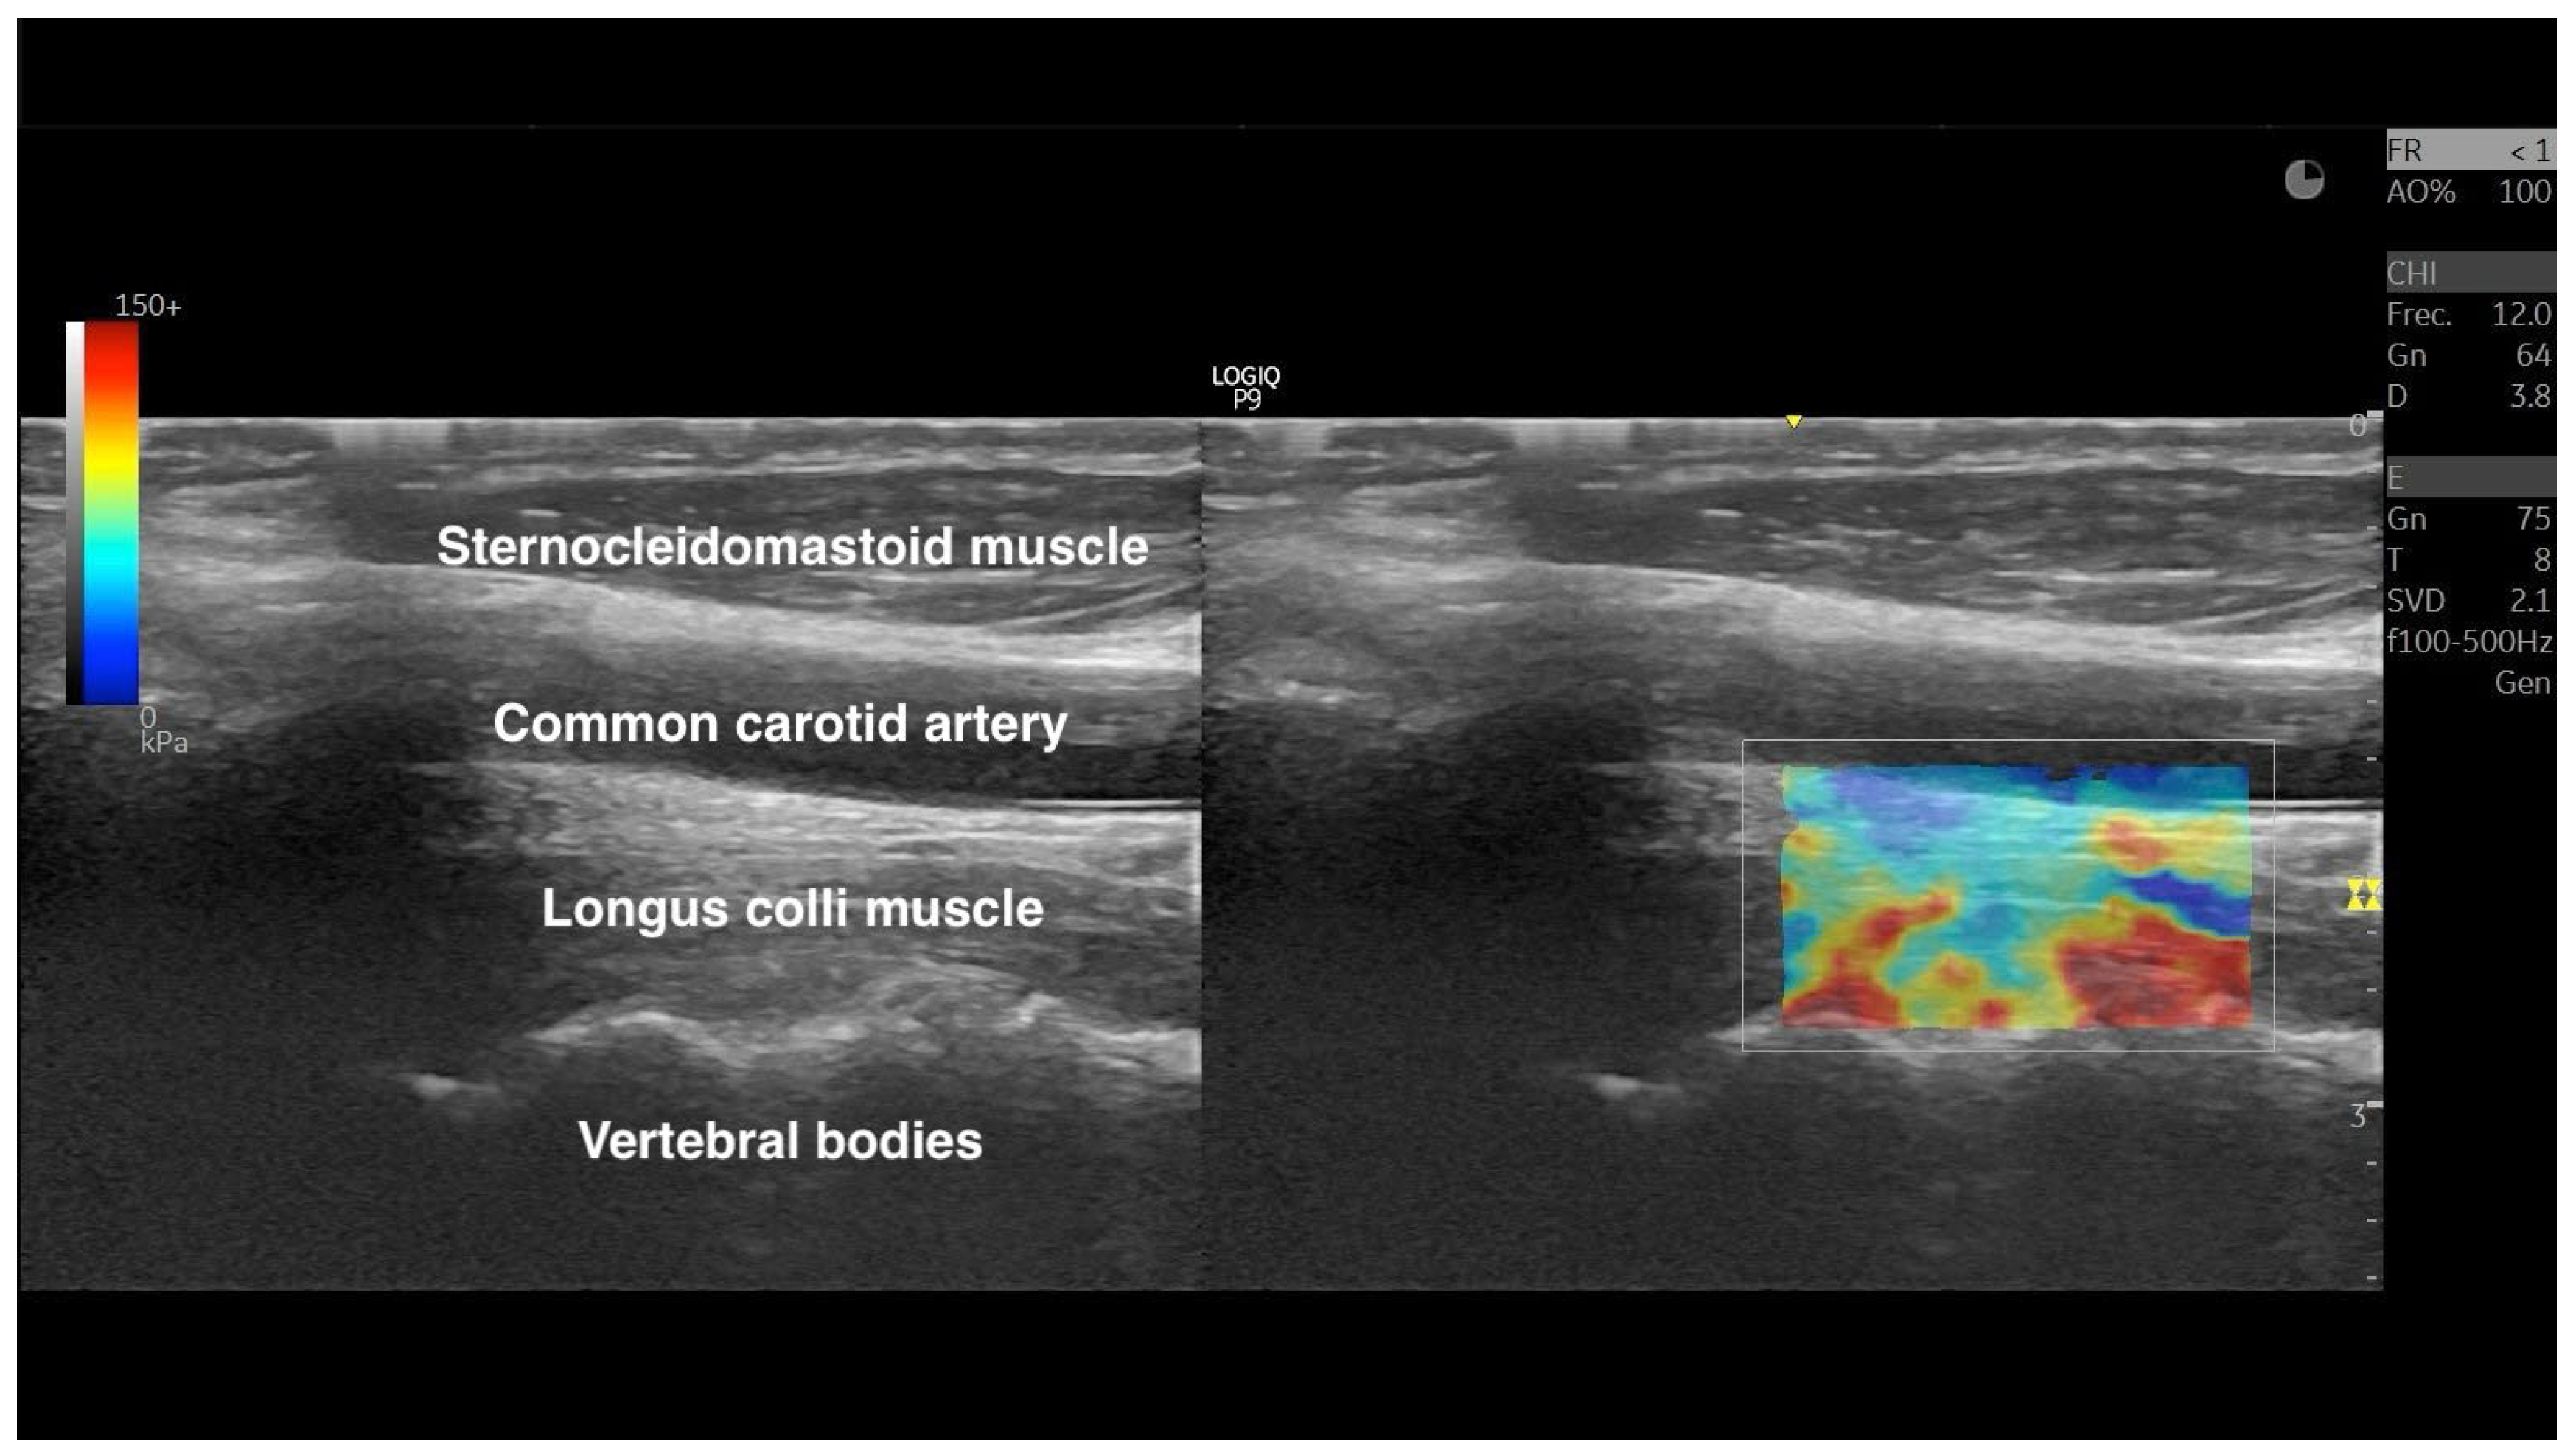

2.4. Shear-Wave Elastography Exam